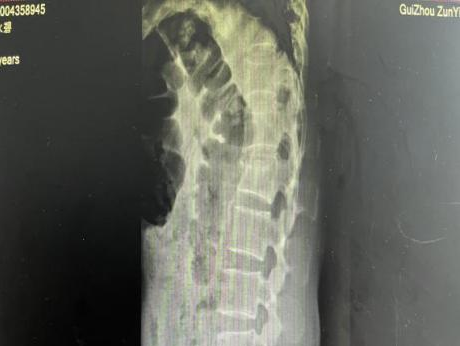

4月23日,贵州航天医院第58次晨读会由我院骨科副主任医师张艳金作学术交流,他以“加速康复指导下的快速手术”为题,详细讲解了老年股骨粗隆间骨折与儿童四肢骨折的临床诊疗难点,结合加速康复外科(ERAS)核心理念,重点阐述了ERAS理念在两大人群中的创新实践,实现患者入院后6至24小时内即可接受手术治疗。针对老年髋部骨折患者,提出通过多学科协作(MDT)与微创手术优化围术期管理,在确保安全前提下缩短术前等待时间,实施精准化麻醉及术后康复方案,可有效降低并发症发生率、改善患者生活质量和预后效果。在儿童骨折领域,强调微创术式与心理干预并行的双轨策略,既减少手术创伤对骨骼发育的影响,同时关注患儿心理疏导,实现生理功能与心理健康同步康复。并通过典型案例的影像学资料与随访数据,直观展示了ERAS理念指导下骨科治疗模式的创新成果。 贵州航天医院骨科 专家简介 赵学平 中共党员,骨科党支部书记、主任,主任医师 临床擅长:从事骨科临床工作30余年,对骨科常见疾病的诊治具有丰富的临床经验。 世界中医药联合会脊柱康复专业委员会常务理事,中华中医药学会整脊分会常务委员,中国中西医结合学会骨伤科分会肢体矫形功能重建与康复专家委员会常务委员,中国研究性医院学会骨科创新与转换专业委员会关节外科学组保髋工作委员会常委,中国康复技术转化及发展促进会骨外科与康复技术转化专业委员会常务委员,泛珠三角区域运动医学联盟(PPRD-SMA)理事会常务理事,中国研究型医院学会运动医学专业委员会委员,贵州省中医药学会整脊分会副主任委员,贵州省中西医结合学会银质针专业委员会副主任委员,贵州省康复医学会骨与关节专业委员会常务委员,贵州省人民医院骨科专科联盟常务理事,贵州省康复医学会骨内科专业委员会常务委员,中华医学会贵州省骨科学会委员,贵州省康复医学会脊柱脊髓专业委员会常务委员,贵州省运动医学分会委员,贵州省康复医学会骨与软组织肿瘤专业委员会委员,遵义市医学会创伤分会副主任委员,贵州省康复医学会骨内科专业委员会遵义地区分会常务委员,遵义市医疗事故鉴定、伤残鉴定、工伤鉴定、司法鉴定专家。 长期从事骨科临床研究及教学工作,在国家级、省部级杂志发表论文20余篇,SCI论文2篇,参与主编骨科专著2部,主持省部级科研项目2项,参与指导省部级、市级科研项目6项。 陈明勇 骨科副主任,副主任医师 临床擅长:从事创伤骨科工作约20年,对骨缺损、骨不连、骨肿瘤、肢体畸形等的肢体矫形重建及功能重建,慢性化脓性骨髓炎的根治治疗、糖尿病足的保肢治疗、快速康复理念(ERAS)下的老年骨折的诊治,四肢复杂骨折的诊治,四肢骨折等微创手术治疗具有丰富的临床经验。 2004年毕业于遵义医学院临床专业,曾在中国人民解放军总医院、广西医科大学第一附属医院、上海第六人民医院骨科进修。中国中西医结合学会骨伤科专业委员会横向骨搬移治疗糖尿病足及微血管网再生学组首届委员,遵义市医学会创伤分会常务委员。 瞿 辉 中共党员,骨科副主任医师 临床擅长:对骨科的常见病、关节外科、脊柱外科及运动医学疾病的诊治具有丰富的临床经验,熟练掌握骨科手术操作技术。 毕业于遵义医学院临床医学系,2005年前往广州中山大学第一附院骨显微医学部进修学习,2011年前往成都华西医院进修学习,并多次在省内外学习骨科相关知识,是中华医学会骨科分会会员。 赵兴东 骨科主任医师 临床擅长:擅长骨科的常见病及各种创伤、四肢骨折创伤修复、骨感染、手足疾病的诊治和手足体表畸形的矫形整复,熟练掌握骨科四肢骨病及创伤的手术操作技术,尤其在四肢关节复杂性损伤、手足外伤、组织缺损创面、难治创面的皮瓣修复方面及平足、高弓足矫形方面及四肢慢性疼痛诊治、康复方面具有丰富的临床经验。 硕士研究生,毕业于遵义医学院临床外科系,2015年前往山东省立医院手足外科进修学习;遵义市医学分会创伤分会第一、二届委员,遵义市手外科医学会第二委届员会常务委员;在省级及省级以上期刊发表文章9篇,参编著作2部,参与主持并完成市级课题1项,参与市级课题2项、省级课题1项。 张艳金 中共党员,骨科副主任医师 临床擅长:从事骨外科工作16年,对复合伤、多发伤的救治、四肢骨干骨折、关节周围骨折、骨肿瘤、骨髓炎等诊治具有丰富的临床经验。 中共党员,硕士研究生,2006年本科毕业于山西医科大学第二临床医学院,2011年研究生毕业于北京军区总医院;在“老年COPD患者合并髋部骨折的诊治”国际合作课题组研究两年,在老年髋部骨折的诊治方面具有丰富的经验,并发表论文6篇;主持遵义市级课题1项,承担遵义医科大学的临床教学工作,获得遵义医科大学优秀带教老师荣誉。编撰有《骨科疾病诊疗精粹》一书,开展2项新技术,编撰地方规范《务川自治县创伤骨科常见疾病诊疗规范》一书。 张俊凯 骨科副主任医师 临床擅长:从事骨科临床工作28年,对创伤骨折、骨感染、骨缺损、骨不连等外科诊治,四肢骨折的微创手术治疗,四肢复杂骨折(如关节内粉碎性骨折、多发骨折等)的损伤控制及手术治疗等具有丰富的临床经验。 1995年毕业于遵义医学院临床专业,2009年前往复旦大学附属医院骨科进修1年。 卢懿明 中共党员,骨科副主任医师 临床擅长:从事骨科工作18年,对创伤骨折、四肢骨折的微创手术治疗、四肢复杂骨折(如关节内粉碎性骨折、多发骨折等)的损伤控制及手术治疗,尤其是髋部骨折的PFNA等微创技术,踝关节骨折、膝关节周围骨折的Mipo微创技术等具有丰富的临床经验,开展了4项新技术,发明6项新型专利技术。 2005年毕业于遵义医学院临床专业,2017年,前往南方医科大学第三附属医院骨科进修半年,回院后运用Mipo技术对骨干骨折及干骺端骨折的治疗技术,同时积极开展骨盆骨折、髋臼骨折腹直肌外侧切口的应用;发表了多篇专业论文,经常参与省内外学术交流会授课,获得医院荣誉称号多个。 邬夏荣 骨科副主任医师 临床擅长:从事骨科工作16年,对四肢复杂骨折、骨肿瘤的诊治,尤其是足踝创伤、慢性踝关节损伤、平足症等诊疗具有丰富的临床经验。 2006年毕业于遵义医科大学临床医学专业,曾在陆军军医大学西南医院进修学习,发表多篇骨科学术论文。 余德怀 中共党员,骨科副主任医师 临床擅长:从事骨科工作10余年,对运动医学、骨关节、脊柱外科常见病、多发病的诊治具有丰富的临床经验。 硕士研究生,2011年毕业于遵义医学院临床医学专业,曾前往遵义医科大学附属医院运动医学专业进修学习;是贵州省医学会运动医学分会青年委员,西部关节镜联盟委员;发表多篇骨科学术论文。 冯 乾 骨科副主任医师 临床擅长:从事骨科工作近20年,熟练掌握骨科多发病及常见病的诊治,尤其对脊柱退变性疾病的诊断及治疗具有丰富的临床经验,主要研究脊柱微创相关治疗方式,能熟练开展椎间孔镜及UBE。 曾前往北京大学第三医院进修学习疼痛及椎间孔镜、首都医科大学友谊医院专业进修脊柱内镜;是贵州省康复医学会第三届脊柱脊髓专业委员会委员;发明专利3项、发表脊柱外科专业论文多篇。 赵小锋 中共党员,骨科副主任医师 临床擅长:从事骨科临床工作11年,对骨科常见病、多发病诊疗有较为丰富的临床经验,擅长脊柱相关疾病诊断及治疗,尤其是颈、腰、腿疼痛疾病诊断及治疗,擅长胸腰椎骨折微创经皮穿刺内固定术、经皮穿刺椎体成形术、经皮穿刺脊柱内镜下腰椎间盘摘除术、单纯开创腰椎间盘摘除术、腰椎滑脱复位椎间植骨椎融合内固定术、腰椎管狭窄减压融合内固定术及人工髋、膝关节置换术等。 2012年毕业于遵义医学院外科学专业硕士研究生,2019年参加“遵义市115医学人才精英计划”于上海交通大学第一附属医院培训学习,2023年于北京大学第三人民医院脊柱外科进修学习,曾获得遵义市优秀医师荣誉称号。 遵义市手外科第一届委员,遵义市医学会创伤分会第一届委员,遵义市医学会创伤分会第二届委员,贵州省康复医学会第三届脊柱脊髓专业会委员,遵义市医学会烧伤与整形外科学分会委员,发表论文5篇,其中国家级核心期刊1篇,SCI论文1篇,主持市级课题1项并结题,参与市级课题2项。 贵州航天医院骨科 简介 基本情况 贵州航天医院骨科组建于20世纪60年代,前身是以创伤和断肢(断指)再植闻名于世的上海市第六人民医院骨科,中国断肢(断指)再植的奠基者、中科院院士陈仲伟等著名专家、学者多次莅临科室指导医疗、教学,是贵州省最早拥有专业骨科技术科室之一,在70年代开展了贵州省首例断肢(断指)再植手术。组建50余年来,诊治患者已逾百万,挽救了无数的伤病员,成为了保障遵义地区人民群众健康的重要支撑。 经过几代人的不懈努力,今天的骨科,已由创伤骨科发展至骨病、骨肿瘤、骨结核等领域,现有脊柱外科、关节外科、四肢创伤、手足外科四个亚专科,成为了集医疗、教学、科研于一体的综合学科,是贵州省临床重点专科、遵义市临床重点专科、遵义市骨科临床医学中心、遵义市基层骨科专科联盟理事长单位。 科室目前开放床位110张,共有医护人员50余人,副高级以上专家18人,硕士研究生15人。拥有一流骨科医疗设备多台,每年不定期选派优秀技术骨干到全国各大知名医学院校进修、学习、参观、交流,并邀请国内、国外知名专家教授来院进行交流、指导,通过不断引进国内外先进的诊疗技术,科室医疗技术水平稳步提升,为广大人民群众提供了优质的医疗服务。 专科特色 骨一科 (一)骨缺损、骨不连的肢体与功能重建 胫骨横向骨搬移技术治疗糖尿病足: (二)慢性骨髓炎的根治治疗 (三)肢体缺血性疾病如糖尿病足、脉管炎的保肢治疗 (四)皮瓣修复 (五)复杂创伤的治疗 (六)老年髋部骨折及小儿骨折快速手术 老年髋部骨折: 骨二科 (一)胸腰椎骨折微创经皮椎弓根螺钉固定术 (二)老年性骨质疏松性患者腰椎滑脱脊柱内固定术(骨水泥螺钉) (三)V形双通道脊柱内镜技术(VBE)腰椎融合术治疗腰椎退行性疾病 (四)老年性骨质疏松性骨折(PVP/PKP)术 (五)人工髋关节置换术 (六)双侧股骨头坏死人工全髋关节置换 (七)右侧全髋置换术后假体周围骨折翻修 (八)人工膝关节置换术 (九)人工膝关节假体松动翻修 (十)关节镜技术 传统手术切口 关节镜技术切口 诊疗范围 骨一科 1.四肢创伤、矫形。 2.手、足踝外科。 骨二科 end